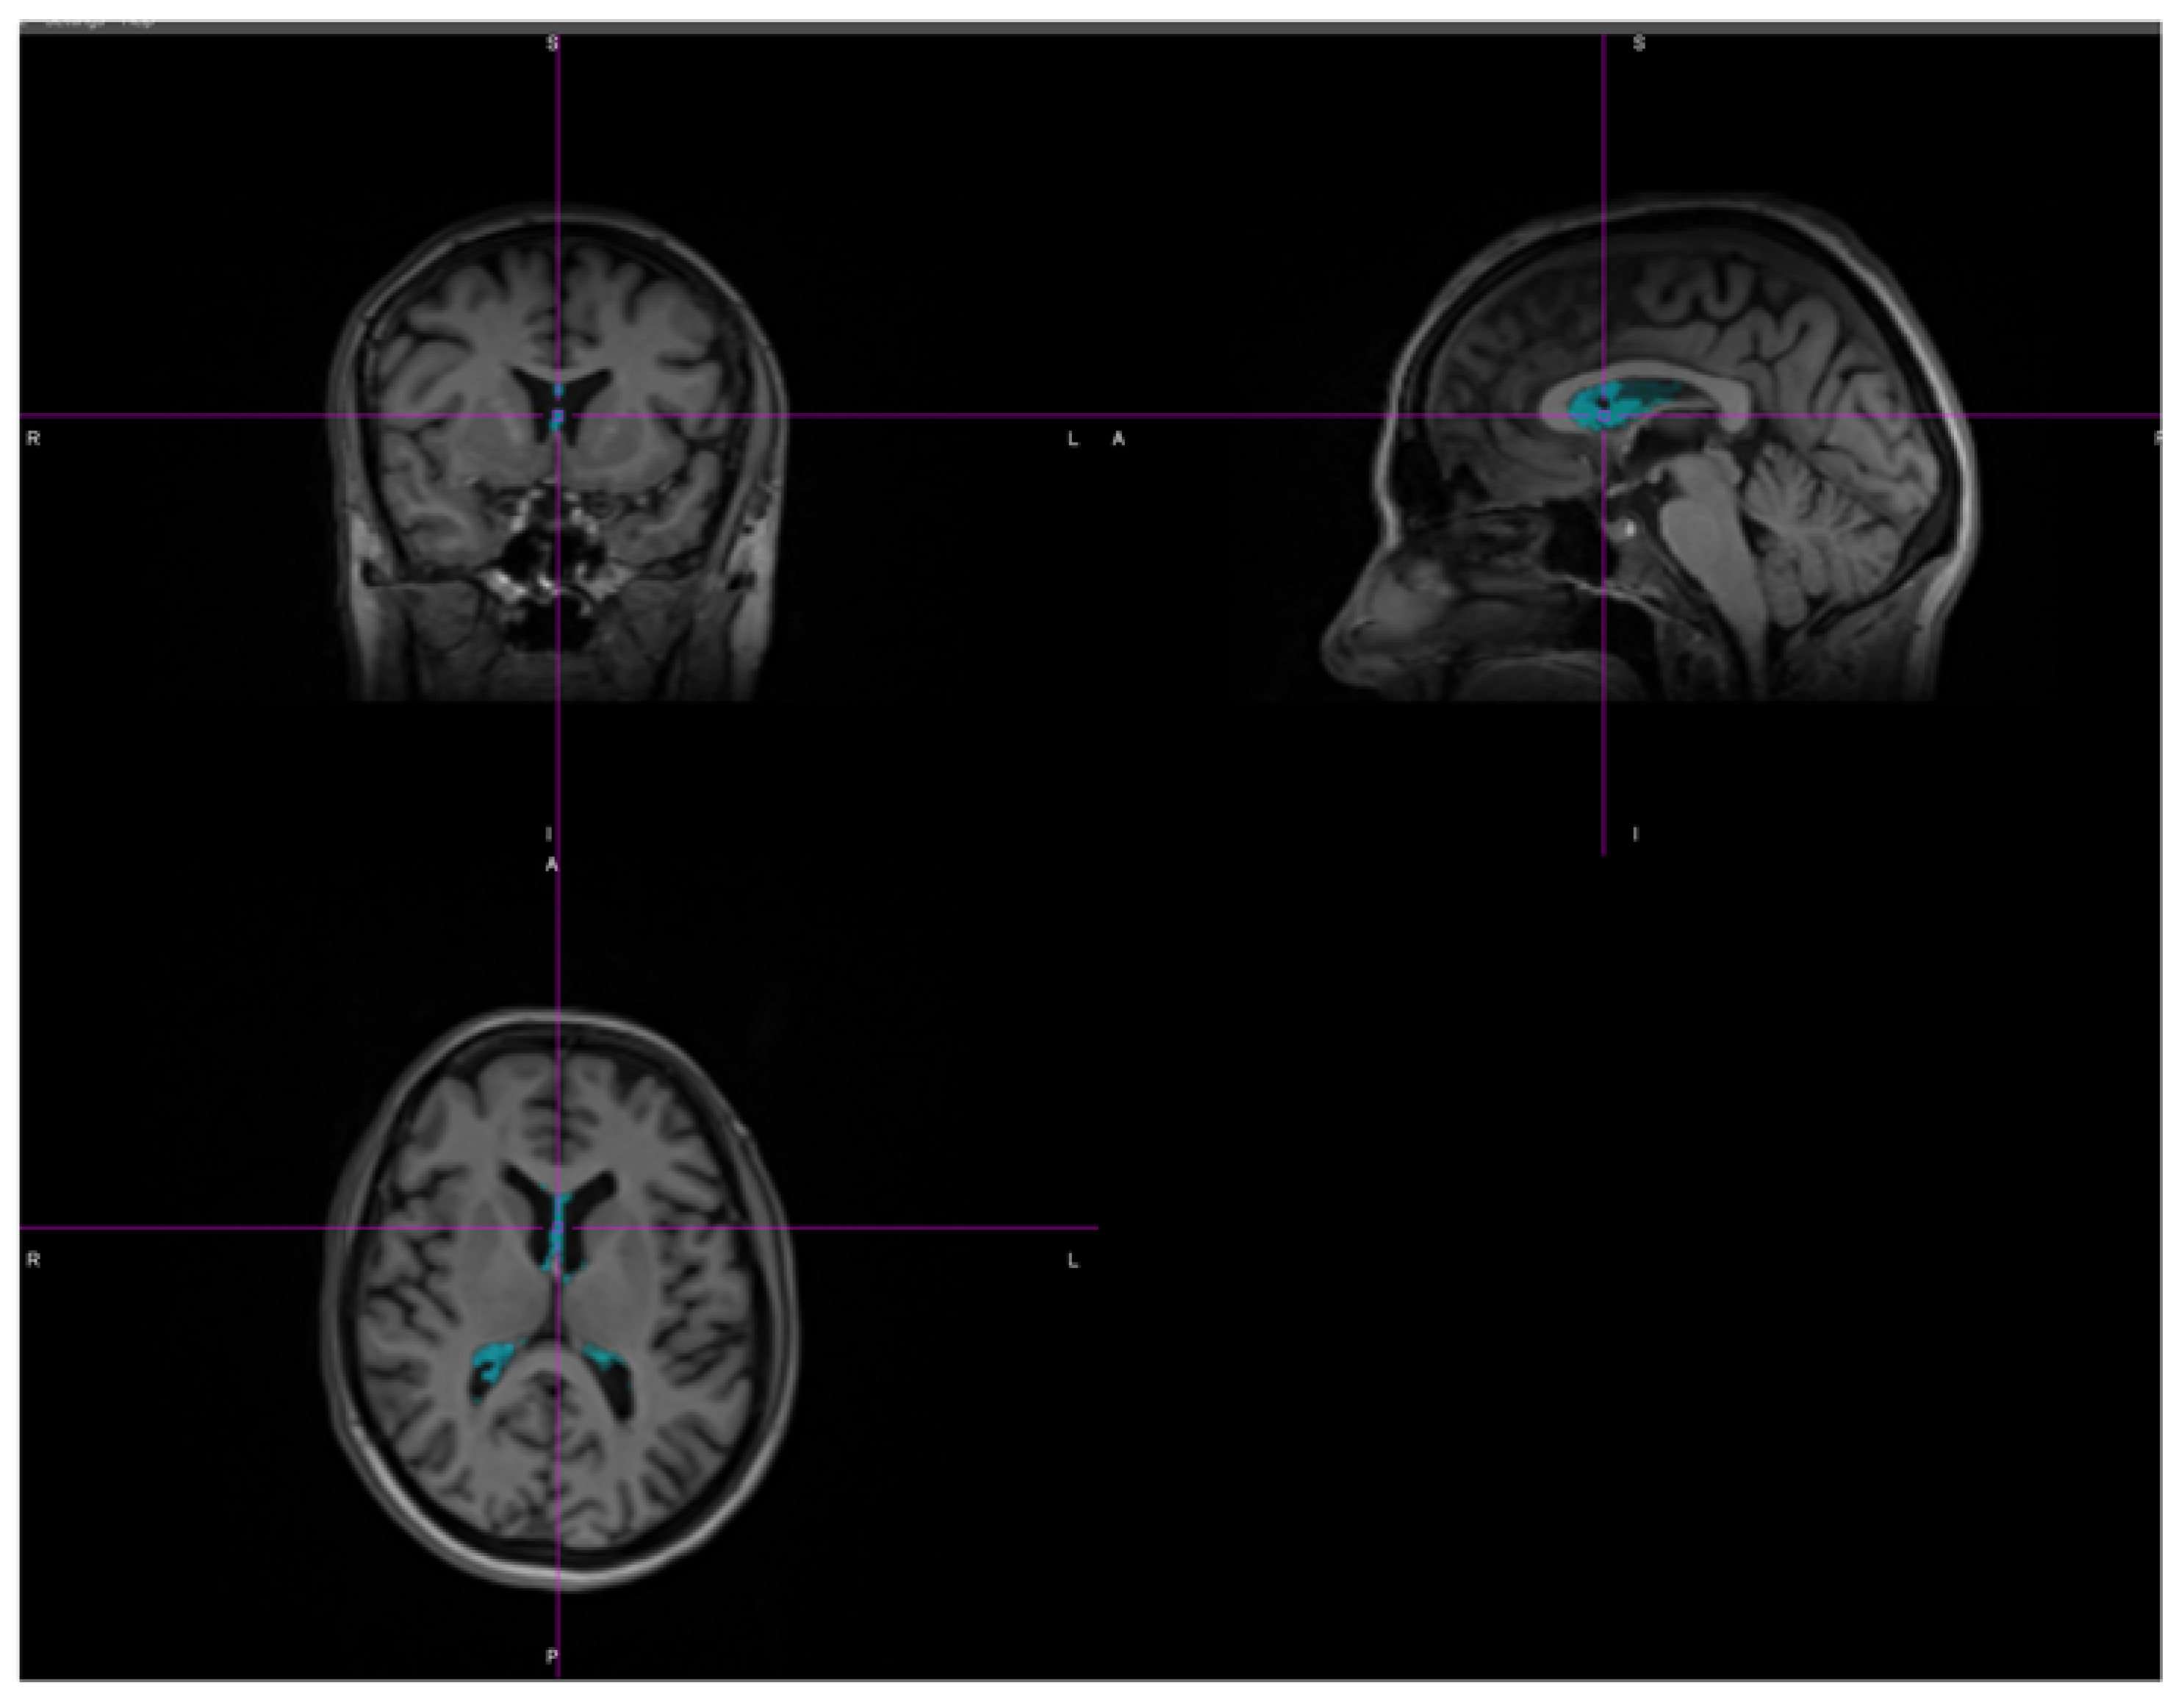

2.2.2. Image Postprocessing

2.2.4. 3DT1 Assessment